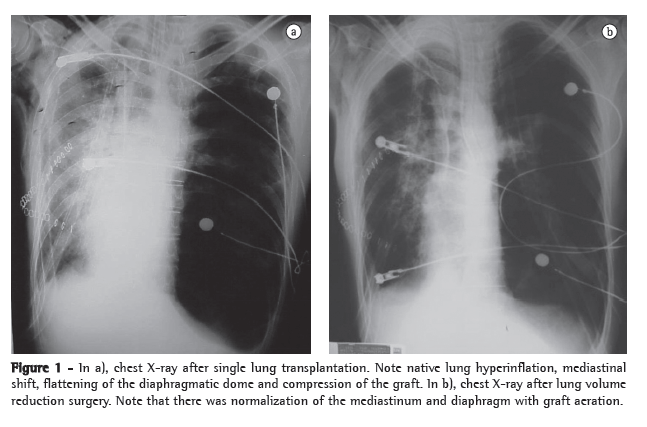

After 7 months on a waiting list, the patient underwent single right lung transplantation, in which the duration of ischemia was 210 min. Immunosuppression was performed with azathioprine, cyclosporine and methylprednisolone. The patient was referred to the ICU and remained intubated for 5 days. However, he developed respiratory failure and required reintubation. There was progressive native lung hyperinflation, with mediastinal shift and worsening of the respiratory pattern. Independent ventilation was employed but did not result in radiological or clinical improvement (Figure 1).

The patient underwent left lung volume reduction surgery to prevent compression of the graft. A linear cutting stapler was used, and multiple wedge resections were performed. Approximately 20% of the parenchyma in the lung apex was removed. The mechanical suture line was reinforced by interposing bovine ­pericardial tissue, as previously described by Cooper.(8)

There was radiological improvement, with expansion of the graft and normalization of the diaphragmatic contour, as well as improvement in pulmonary function (Figure 1). However, the patient developed dehiscence of the anastomosis of the anterior wall of the right main bronchus, together with bronchopleural fistula. The consequent empyema and sepsis led to his death on postoperative day 16.